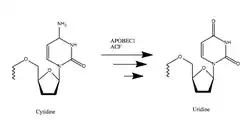

This gene encodes a member of the APOBEC protein family and the cytidine deaminase enzyme family. The encoded protein forms a multiple-protein RNA editing holoenzyme with APOBEC1 complementation factor (A1CF). This holoenzyme is involved in the editing of cytosine-to-uracil (C-to-U) nucleotide bases in apolipoprotein B and neurofibromin 1 mRNAs.[5]

APOBEC-1 (A1) has been linked with cholesterol control, cancer development and inhibition of viral replication.[6] Its function relies on introducing a stop codon into apolipoprotein B (ApoB) mRNA, which alters lipid metabolism in the gastrointestinal tract. The editing mechanism is highly specific. A1’s deamination of the cytosine base yields uracil, which creates a stop codon in the mRNA.

A1 modifies the cytosine base at position 6666 on the ApoB mRNA strand through a deamination.[9] An A1 dimer first binds to ACF, which forms the binding complex that is then able to eliminate the amine group from cytosine.

ACF binds to the mooring sequence, which puts A1 in position to edit the correct residue.[10] By converting cytosine to uracil, A1 changes the codon from CAA, which codes for glutamine during transcription, to UAA, a stop codon.[11] This stop codon yields the much shorter protein ApoB48 instead of ApoB100, as the mRNA is predisposed to transcript.[12] The editing amount, or expression, of A1 performs is correlated with the insulin concentration in the nucleus, the site of modification.[13][14] Tests involving A1 mutants with various deleted amino acid sequences have shown that editing activity is dependent on residues 14 to 35. Like all APOBEC proteins, A1 coordinates a zinc atom with two cysteine and one histidine residues that serve as a Lewis acid. Hydrolytic deamination of the cytosine amine group then occurs, catalyzed by the proton transfer from the nearby glutamic acid residue, and the enzymatic structure is conserved by a proline residue.[10]